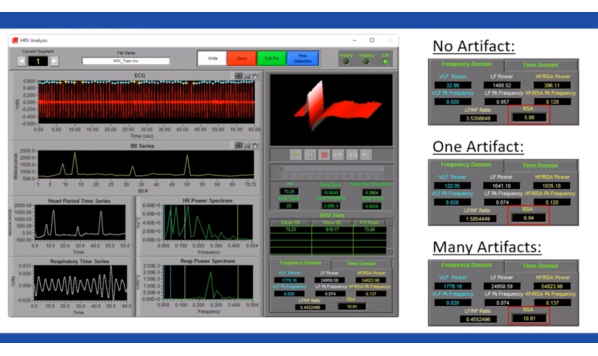

- 64个 实验工具